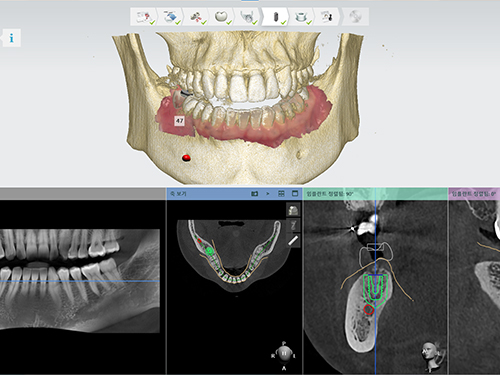

3D CT를 통한 컴퓨터 분석

현재 턱 뼈와 잇몸의 상태를 3차원 입체 영상으로 확인이 가능해

정밀 진단에 따른 오차 없는 수술이 가능